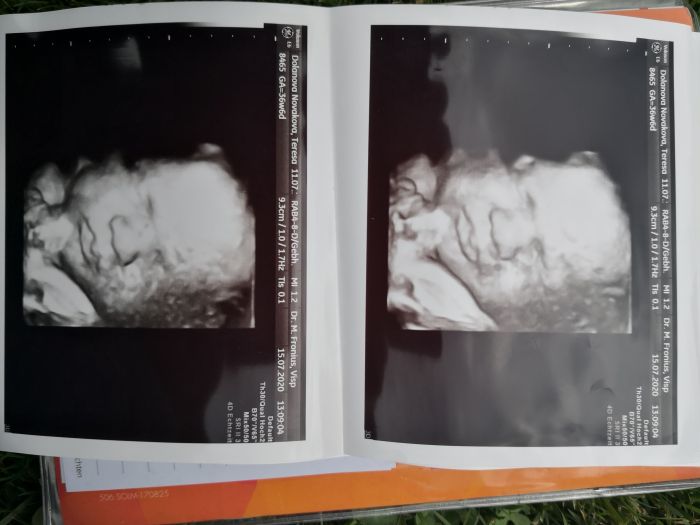

Holky, mam po dalsi kontrole. No a nevim no. Mam bilkovinu v moci. Tlak nastesti ok a otoky uz take ne. Ale trochu obavu mam. Za tyden jdu znovu na moc. Ale pravdou je, ze uz kdyz jsem ji tam davala, tak jsem zirala do kelimku na tu barvu. To jsem v zivote nevidela. Byla to takova ruzovo oranzova. Prcek ma 2,9Kg.Zitra zacinam 38tt. 28.7. mam jit pak na dalsi normalni kontrolu, kde budou delat i ozvy. Pokud tedy do te doby vydrzim. Mam trochu tuseni ze ne. Ale treba prekvapime.Ale rada bych, syn ma 28. narozeniny. Posilam dnesni fotky a preji krasne dny.